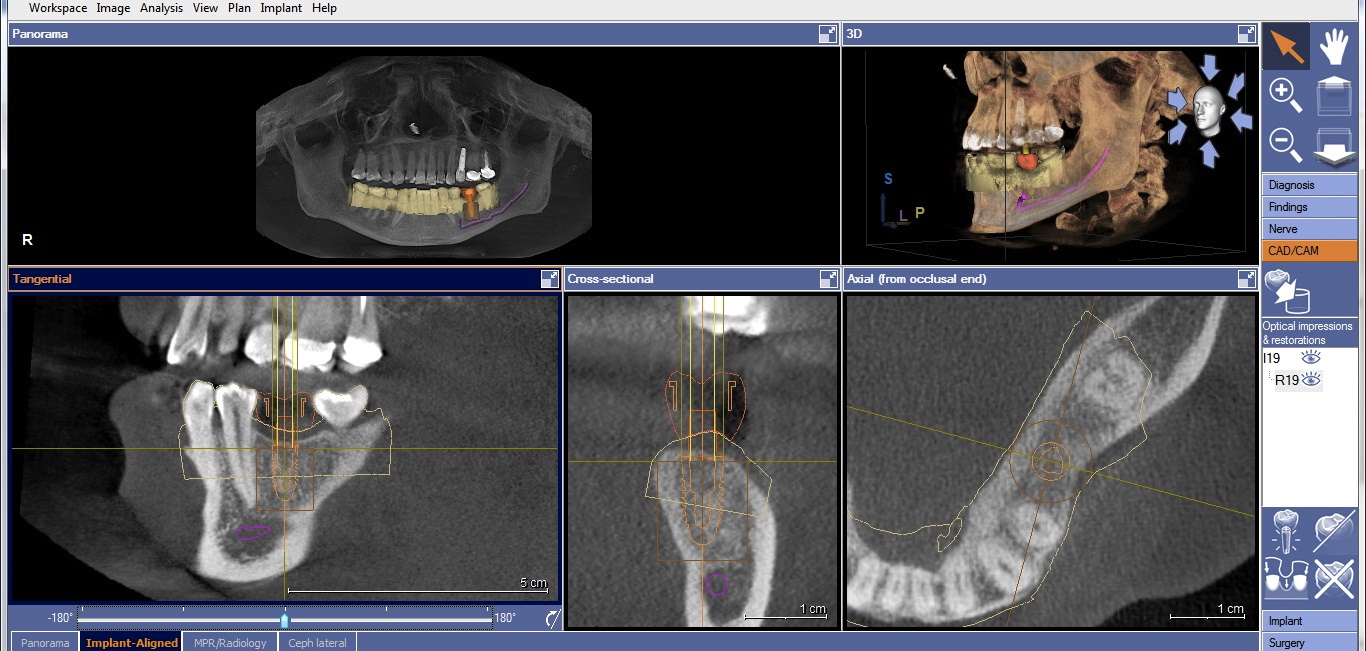

Two factors affect implant depth: distance to the proximal contact and surrounding the implant with 1 mm of bone. The implant platform should be 5 mm or less from the proximal contact for proper papilla formation.21,22 Accounting for prosthetic components, the distance to the occlusal surface should be approximately 7 mm (5 mm abutment + 2 mm ceramic). If placing the restorative platform at the osseous crest does not provide this space, it is necessary to remove bone so the implant can be submerged to proper depth. However, if placing the platform 7 mm from the restorative surface does not result in surrounding the implant with 1 mm of bone, a decision must be made. The deficiency will usually be on the facial. The practitioner must either submerge the implant until there is sufficient bone surrounding it, or if this places the implant too deeply, augment the ridge prior to implant placement. Current guided regeneration techniques can predictably gain up to 5.5 mm horizontally23 and 10 mm to 12 mm vertically.24 Once the implant platform is set, the final apical length of the implant can be adjusted and the digital plan is complete (Figure 3).

CBCT with final implant plan. Note the digital restoration, TiBase abutment, and highlighted IANB.

Figure 3